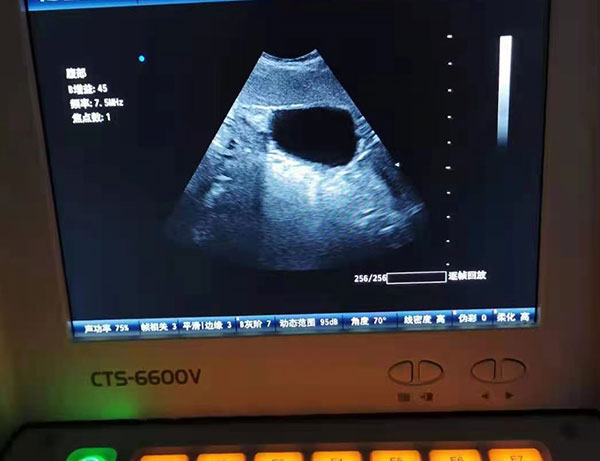

B型超声是应用广、影响大的超声检查。这种方法是在声束穿经人体时,把各层组织所构成的介面和组织内结构的反射回声,以光点的明暗反应其强弱,由众多的光点排列有序的组成相应切面的图像。尤其是灰阶及实时成像技术的采用。灰阶成像使图像非常清晰,层次丰富,一般使用的超声检查仪对囊性或实性的占位性病变均可在5毫米或10毫米大小即可检出,在对比条件好的情况下,如胆囊内息肉样病变,于2~3毫米时即可发现。实时成像功能可供动态观察,随时了解器官与组织的运动状态,犹如一幅连续的电影画面。B超声像图检查应用极广,遍及颅脑、心脏、血管、肝、胆、胰、脾、胃肠、胸腔、肾、输尿管、膀胱、尿道、子宫、盆腔附件、前列腺、精囊、肢体、关节及眼、甲状腺、乳腺、唾腺、睾丸等表浅小器官。产科中对各孕龄胎儿的检查虽然争议颇多,但实际上早已广泛使用,也并无所忧虑的胎儿安全问题发生。B型二维超声图像是以被检查部位的人体解剖结构的回声反射组成,属于形态学诊断,呼伦贝尔动物医院主要用于肿物、畸形、结石及其他能引致局部结构有明显形态改变的疾病。